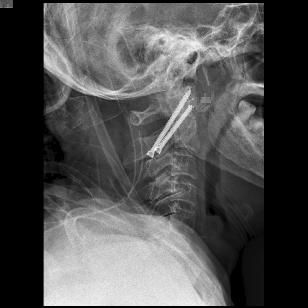

患者经充分咨询了解,选择了枣庄市立医院脊柱外科主任王存平为其治疗。面对患者和家属期盼的目光,王存平明白这是患者最后的希望,故而没有胆怯和退缩,大胆提出了齿状突骨折后路切开复位C1、2椎弓根钉棒系统固定的手术方案。由于患者年龄较大,存在脊柱严重后凸畸形,俯卧位极度困难,全麻插管难度大,麻醉风险极大。麻醉科李传东和宓云飞医师克服重重困难,成功完成麻醉。在他们得力的麻醉和监护下,王存平仔细分离、细心操作,每一步都确保动作稳稳完成,最终成功实施了手术。

经过全程监护和系统治疗,患者术后恢复良好,骨折解剖复位,复查X线及CT显示固定位置佳,术后3天下地行走,术后4天即出院回家休养。

枢椎齿状突骨折后路Margerl手术